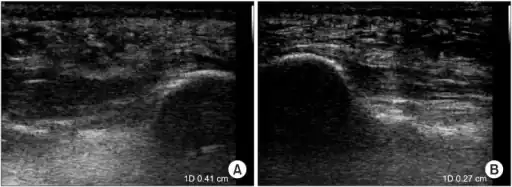

a)Ultrasonographic finding of plantar fasciitis b)normal sonographic finding

Thickened plantar fascia in ultrasound

Imaging

Medical imaging is not routinely needed. It is expensive and does not typically change how plantar fasciitis is managed.[15] When the diagnosis is not clinically apparent, lateral view X-rays of the ankle are the recommended imaging modality to assess for other causes of heel pain, such as stress fractures or bone spur development.[7]

The plantar fascia has three fascicles-the central fascicle being the thickest at 4 mm, the lateral fascicle at 2 mm, and the medial less than a millimeter thick.[18] In theory, plantar fasciitis becomes more likely as the plantar fascia's thickness at the calcaneal insertion increases. A thickness of more than 4.5 mm ultrasound and 4 mm on MRI are useful for diagnosis.[19] Other imaging findings, such as thickening of the plantar aponeurosis, are nonspecific and have limited usefulness in diagnosing plantar fasciitis.[13]